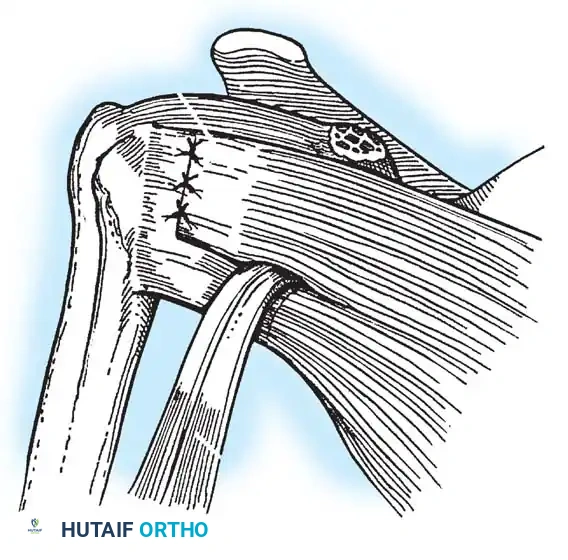

Glenoid Preparation and Labral Repair

The essential step in restoring stability is the anatomical reduction of the capsulolabral complex to a bleeding bone bed on the anterior glenoid rim.

- Debridement: The anterior glenoid neck is decorticated using a motorized burr, rasp, or osteotome to create a bleeding cancellous bed. This promotes robust biological healing of the repaired labrum.

- Mobilization: The scarred, medially displaced labrum (ALPSA lesion) must be fully mobilized using a periosteal elevator until the subscapularis muscle belly is visible anteriorly. The tissue must float freely to be shifted superiorly and laterally.

- Anchor Placement: Suture anchors (typically 3 to 4) are placed along the articular margin of the anteroinferior glenoid (from the 5:30 to 3:00 positions for a right shoulder). Anchors must be inserted at a 45-degree angle to the articular surface to maximize pullout strength and avoid joint penetration.

Capsular Shift and Closure

To address capsular redundancy, an inferior capsular shift is performed.

- The arm is positioned in 30 to 45 degrees of abduction and 20 degrees of external rotation.

- The inferior capsular flap is advanced superiorly and laterally, tensioning the IGHL complex. The sutures from the anchors are passed through the shifted capsule and tied.

- The superior flap is then brought down over the inferior flap in a "pants-over-vest" fashion to reinforce the anterior wall and close the rotator interval.

- The subscapularis split is loosely approximated with absorbable sutures. The deltopectoral interval is closed over a suction drain (if necessary), followed by routine subcutaneous and skin closure.